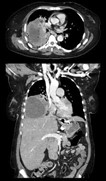

Une tomodensitométrie qui améliore la qualité de l’image et l’efficacité

Le nombre moyen des tomodensitogrammes au Canada a augmenté d’au moins 40% au cours de la dernière décennie.3 Les listes d’attente pour cet examen se sont allongées en raison des confinements forcés par la pandémie au Canada4. Et si nous pouvions faciliter cet examen et en simplifier l’utilisation et rendre plus intelligents les tomodensitomètres déjà livrés pour soutenir les techniciens ainsi que les radiologistes et autres fournisseurs de soins de santé? La question du compromis entre qualité et accès se pose toujours en ce qui concerne la tomodensitométrie. Accroître la qualité de l’image allonge habituellement la durée de l’examen et augmente la dose de rayonnement. Et si nous pouvions accroître la qualité tout en réduisant les listes d’attente par des examens accélérés rendus possibles grâce à une technologie avancée?

La reconstruction d’images intelligente: même par rapport à la reconstruction itérative la plus sophistiquée à base de modèles, les images de TrueFidelitymc CT sont d’une qualité encore jamais atteinte. La reconstruction d’images par l’apprentissage profond (« DLIR ») de GE Santé utilise un moteur de reconstruction basé sur un réseau de neurones profonds pour générer des images de TrueFidelity CT de qualité supérieure.

« Un de nos patients septuagénaire était atteint d’une tumeur cancéreuse nouvellement diagnostiquée envahissant l’atrium gauche. Nous pensions que la composante atriale pouvait être une tumeur ou un thrombus. En raison d’une hémoptysie chez le patient, nous hésitions à prescrire un anticoagulant à cause des risques d’accident vasculaire cérébral. Nous avons effectué une tomodensitométrie cardiaque multiphasique. La DLIR a produit des images vraiment claires qui nous ont permis de confirmer avec assurance le lavage de contraste et le fait que la masse était un élément de la tumeur moins cellulaire et plus nécrotique. L’hypothèse d’un thrombus pouvait donc être écartée. »

– Djeven Deva, MD, radiologue cardiothoracique, Départe- ment d'imagerie médicale, de l'hôpital St Michael, Université de Toronto

Une TEP/TDM qui accroît l’efficacité, aide les cliniciens à détecter une maladie plus tôt et avec plus d’exactitude et améliore l’expérience thérapeutique

Depuis longtemps, l’imagerie moléculaire s’attache non seulement à aider à changer la vie des patients au jour le jour, mais aussi à établir de nouvelles normes au regard des soins cliniques. C’est ce qui rend cette technique si intéressante. La détection de lésions, le faible dosage, les balayages rapides et la résolution de l’image sont des éléments importants, mais il faut aussi guider le traitement, soutenir les patients recevant des soins adaptés, et s’assurer que les nouvelles découvertes au chapitre du diagnostic et des options de traitement peuvent être intégrées dans la pratique thérapeutique.

La TEP/TDM numérique à sensibilité élevée avec la technologie de reconstruction innovatrice: notre vision d’avenir pour la TEP (tomographie par émission de positons) s’oriente vers une technique complètement numérique, de l’acquisition à la reconstruction aux solutions d’analyse ouvertes. Le détecteur numérique LightBurstmc est la prochaine étape de l’avenir numérique de la TEP. Discoverymc MI réunit la sensibilité de la détection numérique et la technologie de la reconstruction innovatrice, la combinaison du temps de vol et de Q.Clear (« BSREM »). On obtient une résolution remarquable et une grande précision quantitative pour améliorer la détection des petites lésions, tout en réduisant de manière significative la dose injectée et le temps d’acquisition.

Des données exactes conduisent à un traitement fiable: Depuis son lancement, Q.Clearmc (« BSREM ») a produit des lectures quantitatives rapides et efficaces, assurant un diagnostic fiable et une évaluation précise de la réponse thérapeutique en améliorant jusqu’à 2 fois plus la précision quantitative (fixation moyenne) et la qualité d’image (rapport signal sur bruit) de la TEP. Utilisant des outils quantitatifs comme Q.Clear qui sont plus précis et constants par rapport aux méthodes conventionnelles, ce système est conçu pour soutenir votre traitement avec des points de données précis. Cela signifie que vos mesures de SUV peuvent devenir plus que des nombres. Ils se transforment en outils utiles à la découverte clinique, au diagnostic et à l’évaluation du traitement fiables.

Gestion numérique des mouvements pour chaque patient: le mouvement respiratoire nuit à environ la moitié de toutes les procédures de TEP/TDM. Les méthodes de synchronisation actuelles sont laborieuses et prennent du temps à installer, ce qui vous contraint à devoir choisir les situations dans lesquelles vous les utiliserez. Par conséquent, seul un faible pourcentage de toutes les procédures affectées par le mouvement tire avantage de la correction du mouvement. Cependant, avec MotionFreemc, chaque patient profite d’une réduction du mouvement pendant son examen et d’images exceptionnellement claires.

MotionFree est la toute première solution numérique de gestion des mouvements respiratoires. Cette technique surveille en continu les mouvements respiratoires dans chaque procédure de TEP/TDM, et si elle détecte une anomalie, elle optimise automatiquement l’examen l’image finale en temps réel. MotionFree est la nouvelle norme en imagerie TEP et un outil essentiel pour améliorer les résultats.